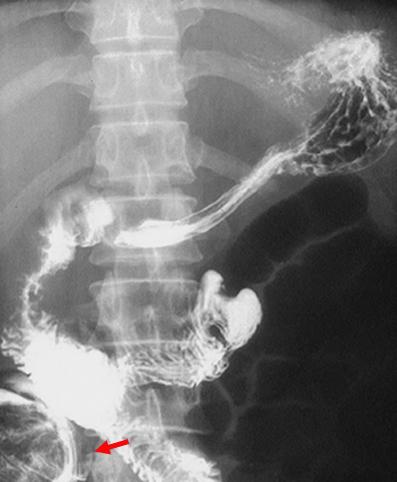

疾患(病理主体)の分類転移性腫瘍/

部位(臓器別)小腸/空腸

検査方法X-P

病変の最大径(ミリ)40以上